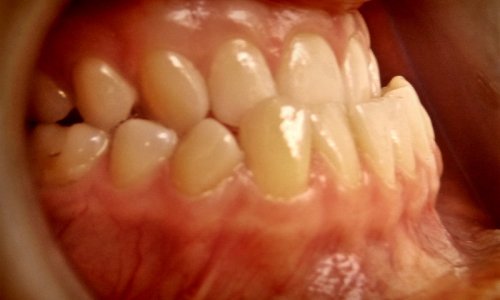

Idealny Zgryz

Rezultat: Leczenie zespołowe dało pozytywny efekt zarówno w odniesieniu do zgryzu, jak i do profilu twarzy.